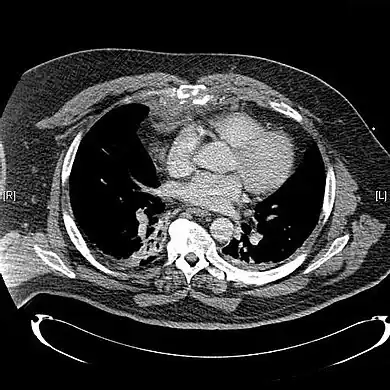

Computed tomography identifying displaced sternal fracture.

CT scan showing a comminuted sternal fracture.[14]